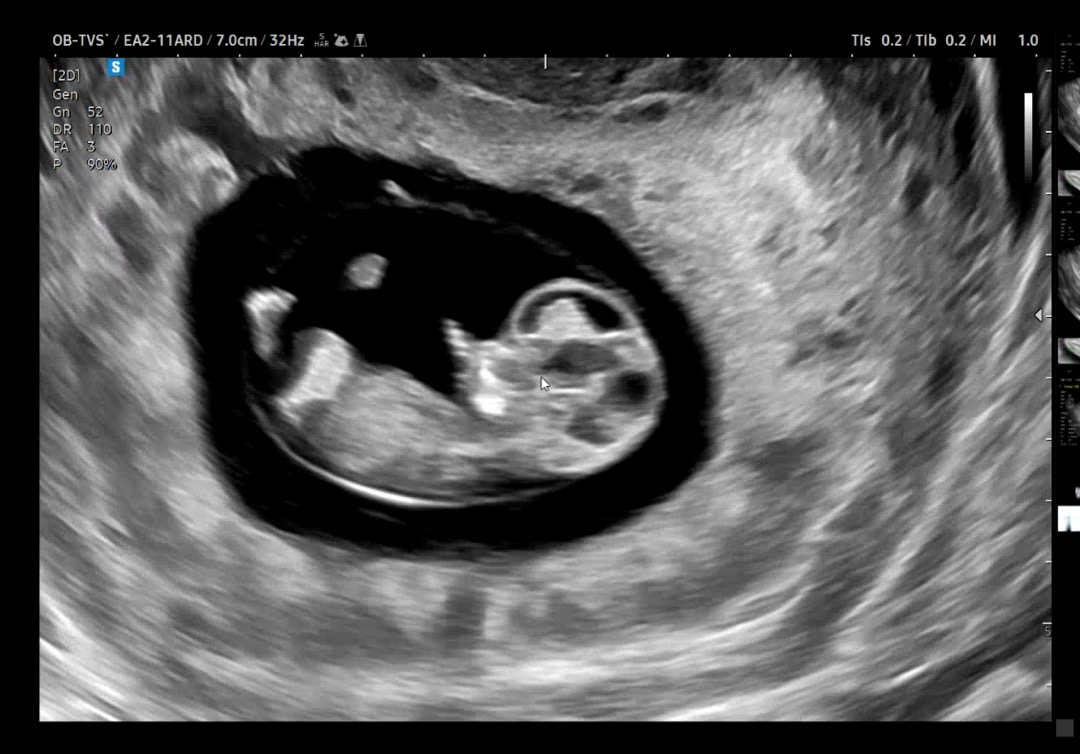

젤리곰보러 갔는데 손가락이 꼬물💛

젤리곰 보러 3주만에 갔는데 언제 이렇게 팔다리도 자라고 손가락도 생겼는지🥹 하리보는 놓쳤지만 너무 귀여워요😍 어제 9주 3일에서 9주 6일로 바꾸어주셔서 이제 벌써 10주가 됐네요 무럭무럭 자라렴🐰❤️

입덧 핑계로 땡기는 피자랑 콜라 마셨던 제 자신이 너무 창피해지더라구요🥹 아기는 이렇게 열심히 자라고 있었는데🥲 건강하게 잘 챙겨먹어야겠어요

팔다리 아직 째깐해서 젤리곰 아닌가요~?^^ 넘넘 귀여운 아기 건강하게 자라렴!